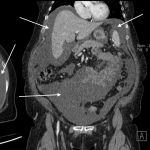

ABDOMINAL/PELVIC CT-SCAN WITH ONLY ORAL CONTRAST

Key features of ascites seen in this imaging modality are:

- Density similar to water (transudative ascites): typically between -10 and + 10 HU

- Density slightly above water (exudative ascites): can be above 15 HU

- Does not enhance with oral contrast: typically this should not occur (unless there is bowel perforation/connection/fistula to the GI tract and the peritoneum).

The gallery below organizes examples of how ascites will appear on a abdominal/pelvic CT-scan with the usage of only oral contrast. Click on the thumbnails below to open up the gallery: